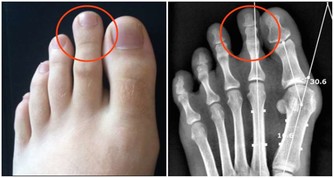

2、口腔健康:牙齒堅固

口腔衛生,基本上沒有齲齒和其他口腔疾病。中醫認為,“腎主骨”,“齒為骨之餘”,牙齒是骨的一部分,與骨同源,所以牙齒也依賴腎中精氣來充養。腎精充足,則牙齒堅固、齊全;精髓不足,則牙齒鬆動,甚至脫落。